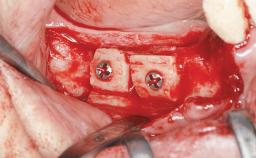

A 47-year-old woman who had suffered from aggressive periodontitis requiring a number of periodontal interventions over more than 10 years was referred by her general dental practitioner and periodontologist for bone augmentation and implant therapy. Her failing dentition had already been scheduled for extraction. The patient expressed a desire for implant-supported fixed restorations and esthetic improvement of her lower face. She had agreed to consult with a maxillofacial surgeon after the referring dentist had suggested bone augmentation. An initial examination by the maxillofacial surgeon revealed mobility of all residual teeth in a patient who was very unhappy with the function of her removable partial dentures. Due to periodontally migrated flaring teeth and loss of occlusal support, the vertical dimension of occlusion was dramatically reduced. The patient was displeased with her lower face because of deepened nasolabial, commissural, and supramental folds.

Bone Augmentation Horizontal|Sinus Floor Elevation|Staged|Vertical

Augmentation Materials Autogenous chips|Autogenous block(s)|Xenogenous|Membrane